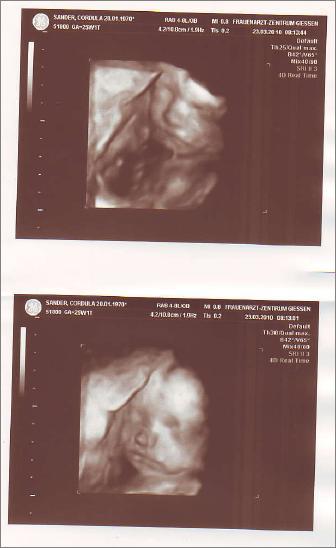

Heute hatte ich VU und 4D Ultraschall. Was war das aufregend!!! Leider konnten wir nur kurz gut was erkennen weil Madame sich sobald sie bemerkt hat sie wird fotografiert die Hände vors Gesicht genommen hat und auch nicht dazu bewegt werden konnte sie runter zunehmen ;-)

In 4 Wochen probieren wir es dann nochmal. ;-) Aber ein schönes Bild hab ich bekommen und versuch es gleich hoch zu laden.